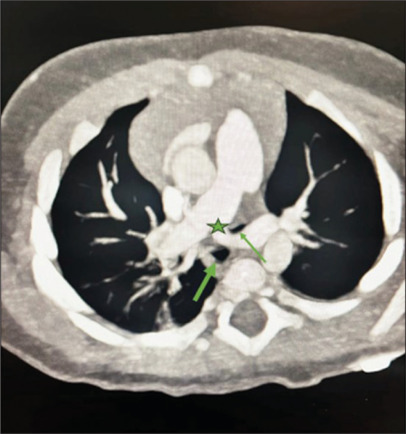

Imaging of a baby with recurrent airway infections.

Stridor, choking episodes and recurrent respiratory infections are common causes of referral for echocardiographic evaluation of the cardiovascular system. Vascular anomalies are rare but important causes of airway symptoms and/or feeding difficulty in young infants and should be carefully evaluated during echocardiogram.